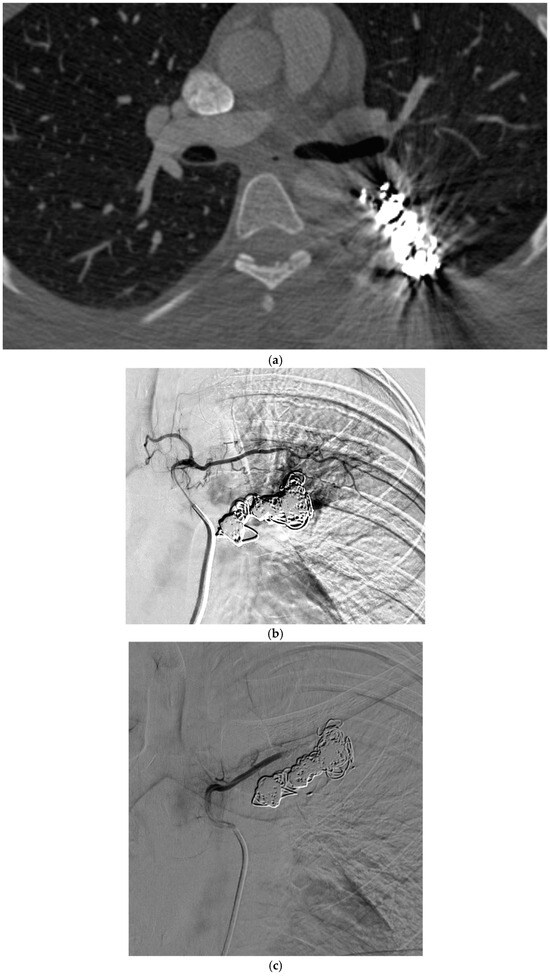

Figure 4.

A 26-year-old female with HHT and previously embolized PAVMs, presents with hemoptysis. (a) CT of the chest, axial view, demonstrates pulmonary hemorrhage surrounding the embolization coils. (b) Pulmonary angiogram demonstrates multiple systemic collaterals arising from a left intercostal artery, filling the venous outflow beyond the previously embolized coils. (c) The intercostal artery is successfully occluded with gelatin sponge slurry.

These criteria were confirmed angiographically, with criteria 1 demonstrated angiographically as recanalization (Figure 2a,b). Criteria 2, combines accessory feeding arteries and pulmonary collaterals together as they are generally difficult to differentiate angiographically (Figure 3a,b). Criteria 3 is angiographically shown as perfusion of the PAVM outflow via injection of systemic arteries (Figure 4a,b).

The proposed reintervention criteria were based off the greater than 30 years of experiences at a single large HHT center of excellence. The reintervention criteria described in this paper may be used as general guidelines but may not always be generalized to each patient and practice. Additionally, as the population in this study only included adults, it may not be applicable to the pediatric population. The first indication of reintervention requires experience evaluating the embolic devices. A contrast-enhanced chest CT must be windowed in such a way to see the degree to which contrast flows through the embolic device(s). If a column of contrast is measured to be approximately greater than 2–3 mm through, this would suggest a need for reintervention (Figure 2a,b). This may be difficult to determine, and evaluation of the scout images can be helpful to see how well the coil is packed. The second indication for reintervention involves the treatment of accessory pulmonary collaterals (Figure 3a–e). Accessory pulmonary collaterals are a result of adjacent pulmonary vessels which fill the feeding artery or sac beyond the embolic device(s). When this collateral vessel is greater than 2–3 mm, reintervention is indicated. The third criteria involve the treatment of systemic collaterals (Figure 4a–c). This is by far the most complicated issue to address and was the cause of the sole case of iatrogenic stroke. Luckily these systemic collaterals are rare, with a lifetime prevalence of 1.0% [13]. The author’s institutions experience treating these systemic collaterals was previously published. Patients with previously treated PAVMs presenting with hemoptysis are often due to systemic collaterals. In some cases, these lesions can be clearly identified on a chest CTA; however, this is not always the case and therefore a clinical presentation of hemoptysis is enough to indicate reintervention and interrogation of the systemic arteries. Understanding the best way to treat these lesions is an ongoing process.